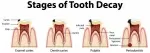

В итоге болезненным остался один передний зуб с пломбой. Сильно реагировал на горячее и теплое. Начинал прямо ныть. В нем была пульсирующая боль в течение дня. Ухудшения в зависимости от времени суток не заметила. Сплю нормально. Сейчас больно жевать и трогать его, особенно больно на кончике зуба, где ребрышки. Больно чистить щеткой. Если ничего не делать, то ощущаю легкое онемение и легкую пульсацию. На пломбе есть небольшая коричневая черточка, прямо посередине. Пломбе более 10 лет.

Без клинического осмотра поставить диагноз не просто. Но в области апекса центрального резца определяется небольшое расширение периодонтальной щели, под пломбой визуализируется потемнение. Не исключен рецидив кариеса с осложнением в виде гангренозного пульпита. Рекомендуем обратиться к стоматологу-терапевту.